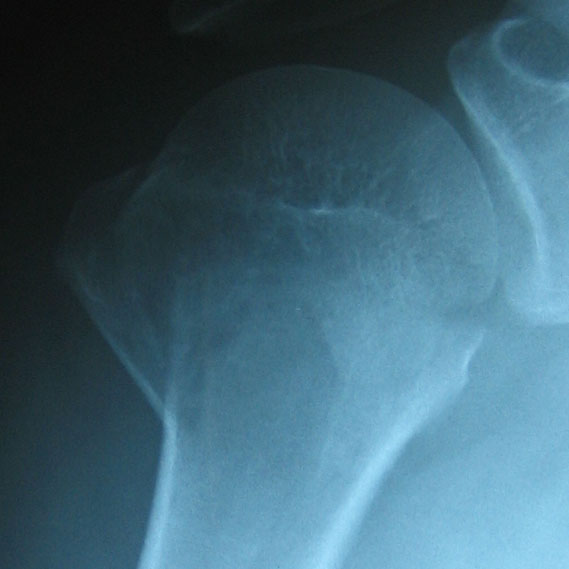

³ä¤ì¤¿¾åÏÓ¹ü¤Î¼Ì¿¿

¤É¤¦¤â¤³¤Î¡¢±¦¸ª¤Î¡¢´Ý¤¤¤È¤³¤í¤¬¥«¥ê¥á¥í¤ß¤¿¤¤¤Ë³ä¤ì¤¿¤è¤¦¤Ç¤¹¡£¤½¤ì¤Ç¡¢ÏÓ¤¬³°Â¦¤Ë¾¯¤·³«¤¤¤Á¤ã¤Ã¤¿¤é¤·¤¤¤Ç¤¹¡£¤¢¤ì¡¢¤³¤Î·ä´Ö¡Ê±¦¤Î¤ï¤­¤Î²¼¤Ë¤¢¤¿¤ëÉôʬ¤Î·ä´Ö¡Ë¤ÏÀΡʰ콵´ÖÁ°¡Ë¤Ï¤Ê¤«¤Ã¤¿¤Î¤«¤Ê¡©¤¢¤ó¤Þ¤ê¸«¤¿¤³¤È¤Ê¤¤¤Î¤Ç¤ï¤«¤é¤Ê¤¤¤ó¤Ç¤¹¤¬(^^;

¤Ç¡¢¤â¤¦°ì²Õ½ê¤Á¤ç¤Ã¤ÈÀޤ줿¤È¤³¤í¤¬¤¢¤ë¤é¤·¤¤¤Î¤Ç¤¹¤¬¡¢¤½¤Á¤é¤Ïº³ºÙ¤Ê¤È¤³¤í¤Ê¤Î¤ÇÌäÂê¤Ê¤¤¤é¤·¤¤¤Ç¤¹¡£

»²¹Í¤Þ¤Ç¤ËÀÞ¤ì¤Æ¤Ê¤¤¾åÏÓ¹ü¤Î¥¤¥é¥¹¥È¤ò¸«¤Ä¤±¤Æ¤­¤¿¤Î¤ÇźÉÕ¤·¤Æ¤ª¤­¤Þ¤¹¡£½Ðŵ¤Ï·Ä±þµÁ½Î¿®Ç»Ä®ITC¤Î¡ÖHumerus¡Ê¾åÏÓ¹ü¡ËHumerus¡¡¤¸¤ç¤¦¤ï¤ó¤³¤Ä¡×¤È¤¤¤¦¥Ú¡¼¥¸¤Ç¤¹¡£

º£Æü¡¢ÀìÌç²È¤Ë¸«¤Æ¤â¤é¤¤¤Þ¤·¤¿¡£¾åÏÓ¹ü¤Î¡¢¸ª¤ËÆþ¤Ã¤Æ¤¤¤ë´Ý¤¤Éôʬ¤¬³ä¤ì¤Á¤ã¤Ã¤¿¤è¤¦¤Ê´¶¤¸¡©¤¢¤È¡¢¤Ê¤ó¤«¸ª¤ÎÊ̤ÎÉôʬ¤â¤Á¤ç¤Ã¤ÈÀÞ¤ì¤Æ¤¤¤ë¤ß¤¿¤¤¤Ç¤·¤¿¤¬¡¢¤½¤Á¤é¤ÏÊ̤ˤɤ¦¤Ç¤âÎɤ¤¤é¤·¤¤(^^;¡¡¤È¤ê¤¢¤¨¤º¼ê½Ñ¤ÏÉÔÍפ¸¤ã¤Ê¤¤¤«¡¢¤È¤Î¸«Î©¤Æ¤Ç¤·¤¿¡£°ì½µ´ÖÍͻҤò¸«¤ë¤È¤Î¤³¤È¤Ç¤·¤¿¡£¤Ê¤Î¤Ç¡¢Íè½µ¤â¤¦°ìÅٹԤäƼ̿¿¤ò»£¤Ã¤Æ¤«¤é¡¢¤â¤¦¤Á¤ç¤Ã¤È¸·Ì©¤Ë¿ÇÃǤ¹¤ë¤³¤È¤Ë¤Ê¤ê¤½¤¦¤Ç¤¹¡£

Àޤ줿¤Î¤Ï¾åÏÓ¹ü¤Î¤Ä¤±º¬¡£ÌÀÆü¡¢É±¡¹Ô¤Ã¤Æ¤­¤Þ¤¹¡£